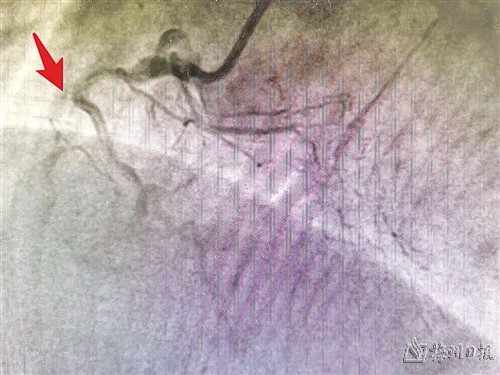

严重狭窄的冠状动脉

前段时间,梅州市人民医院心脏血管外科收治了一位74岁男性患者,详细检查发现,该患者的病情非常棘手,心脏血管以及脑部供血的两条颈动脉已经严重狭窄,同时还合并有贫血、慢性肾功能衰竭、糖尿病、高血压等多种基础疾病,面临着心梗、脑梗双重风险。